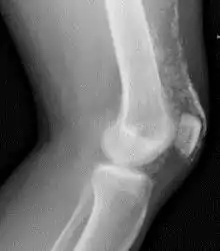

Vue aux rayons X du genou d'un patient atteint de dermatopolymyosite